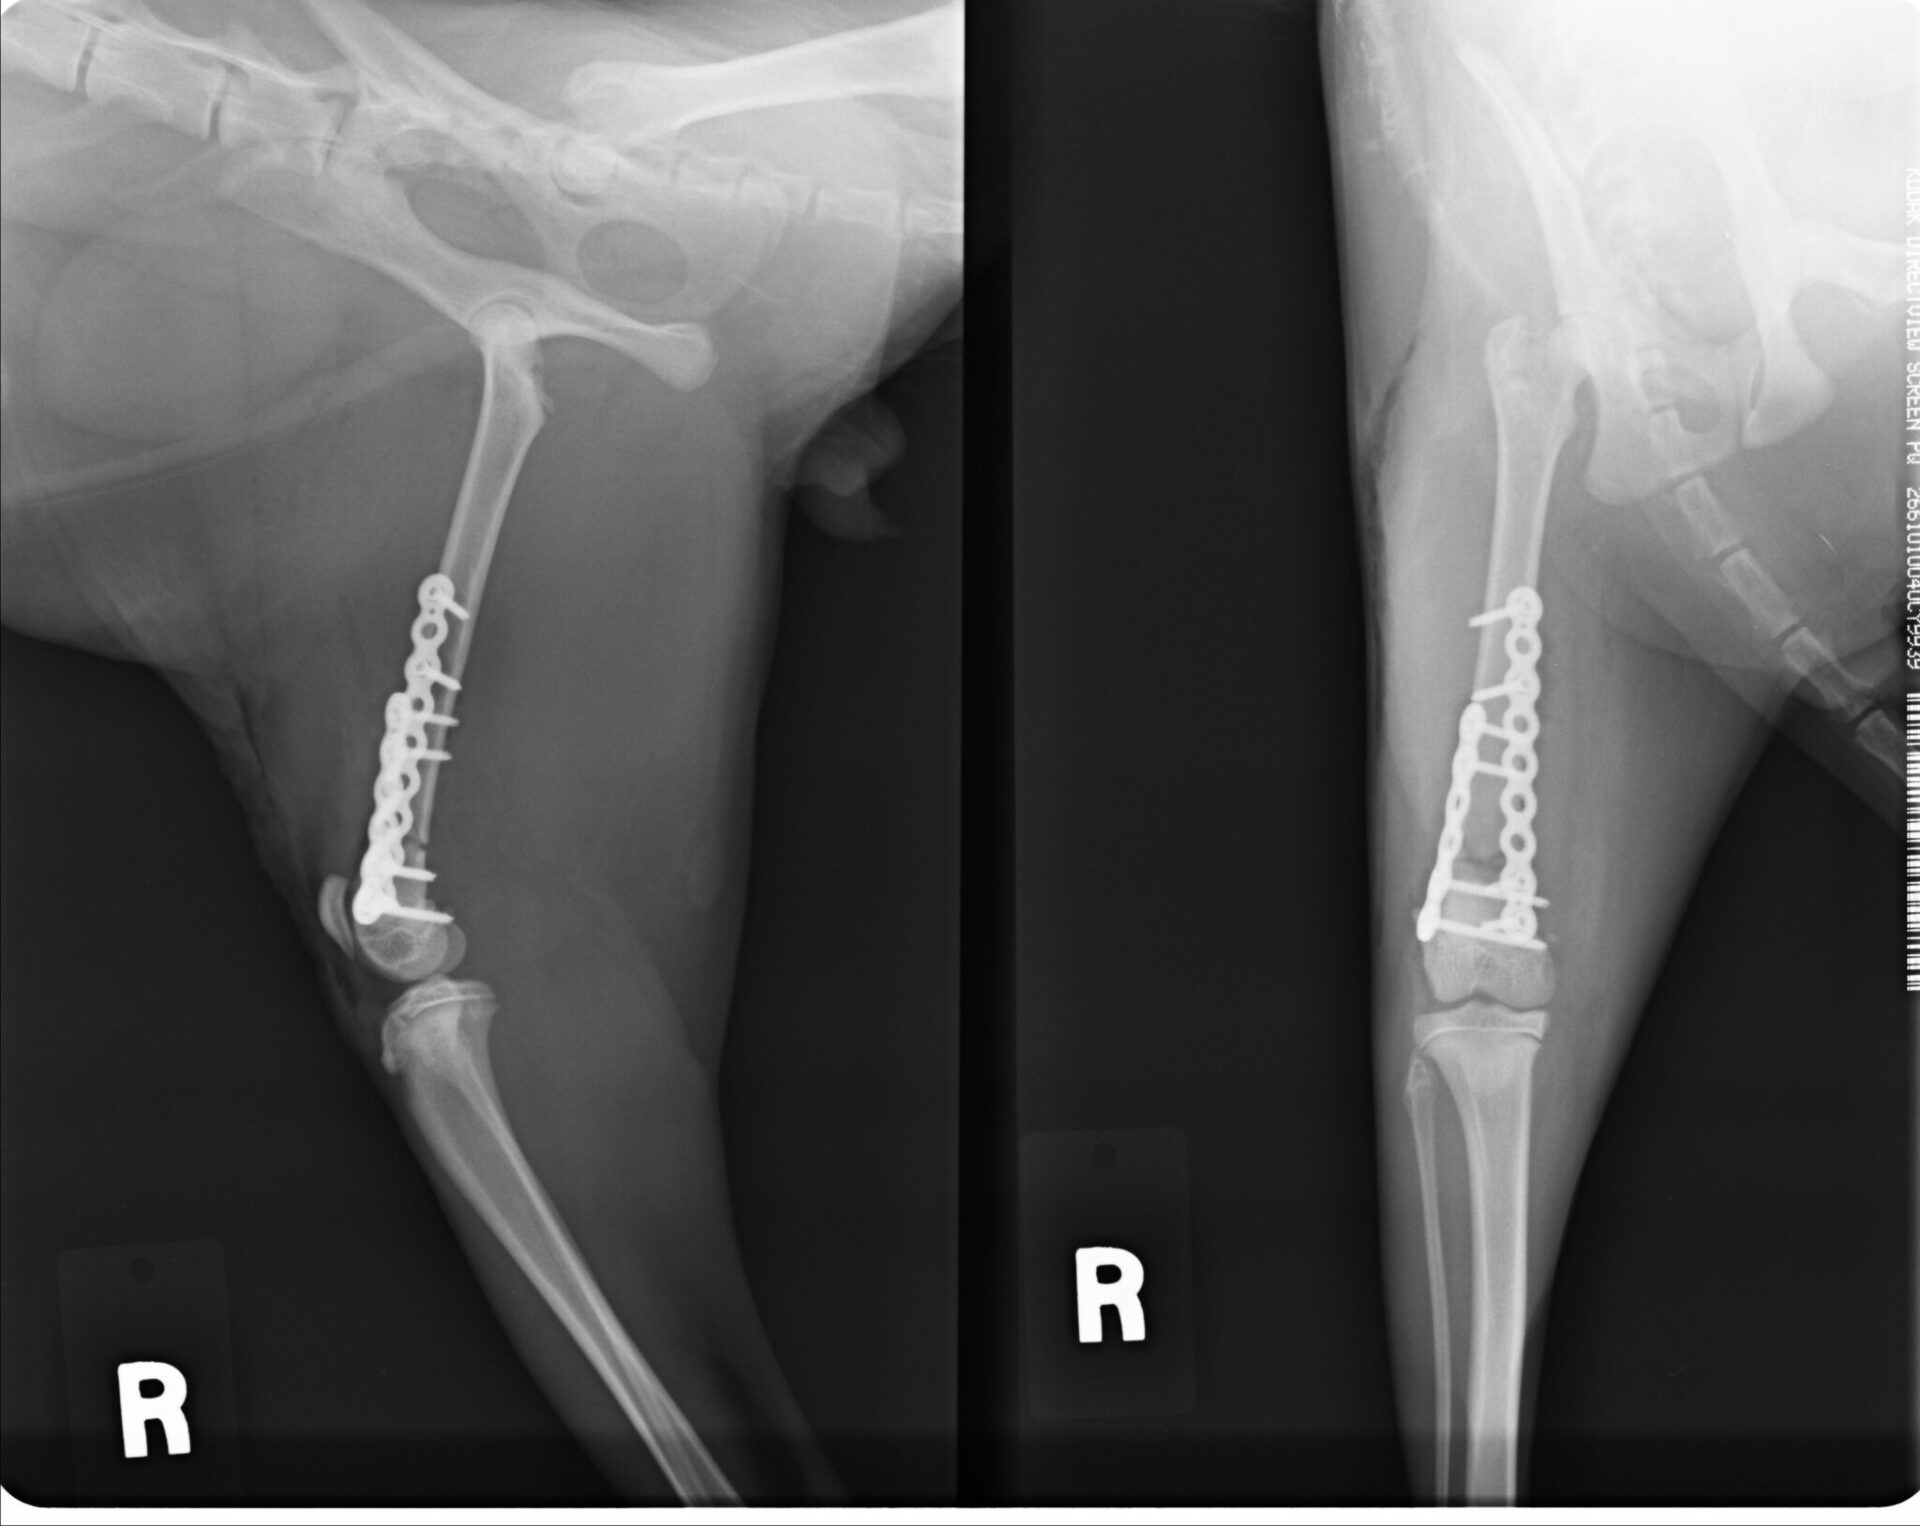

前十字靭帯断裂制動術(TPLO法・術前プランニング)

骨切りを行う前にインプラントの適応など入念な手術計画が必要です

前十字靭帯断裂制動術(TPLO法・術後)

TPLOをメインの手術手技として取り組んでいます。